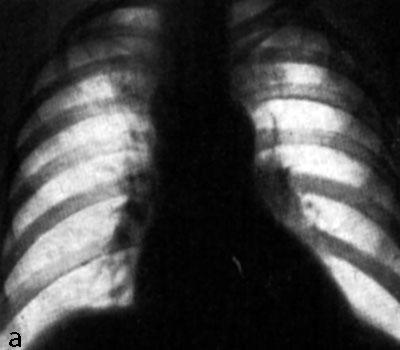

Рентгенологические изображения и синдромы патологии легких

Раздел: Кадры-подсказки